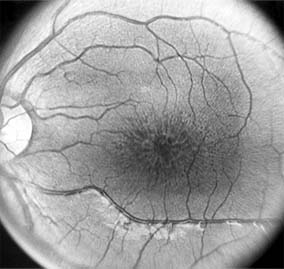

Chapter 10: Retina DISEASES OF THE MACULA AGE-RELATED MACULAR DEGENERATION Age-related macular degeneration is the leading cause of permanent blindness in the elderly. The exact cause is unknown, but the incidence increases with each decade over age 50. Other associations besides age include race (usually Caucasian), sex (slight female predominance), family history, and a history of cigarette smoking. The disease includes a broad spectrum of clinical and pathologic findings that can be classified into two groups: nonexudative ("dry") and exudative ("wet"). Although both types are progressive and usually bilateral, they differ in their manifestations, prognosis, and management. The more severe exudative form accounts for approximately 90% of all cases of legal blindness due to age-related macular degeneration. 1. NONEXUDATIVE MACULAR DEGENERATION Nonexudative age-related macular degeneration is characterized by variable degrees of atrophy and degeneration of the outer retina, retinal pigment epithelium, Bruch's membrane and choriocapillaris. Of the ophthalmoscopically visible changes in the retinal pigment epithelium and Bruch's membrane, drusen are the most typical (Figure 10-1). Drusen are discrete, round, yellow-white deposits of variable size beneath the pigment epithelium and are scattered throughout the macula and posterior pole. With time, they may enlarge, coalesce, calcify, and increase in number. Histopathologically, most drusen consist of focal collections of eosinophilic material lying between the pigment epithelium and Bruch's membrane; they therefore represent focal detachment of the pigment epithelium. In addition to drusen, clumps of pigment irregularly dispersed within depigmented areas of atrophy may progressively appear throughout the macula. The level of associated visual impairment is variable and may be minimal. Fluorescein angiography demonstrates irregular patterns of retinal pigment epithelial hyperplasia and atrophy. Electrophysiologic testing in most patients is normal. There is no generally accepted treatment or means of prevention of this type of macular degeneration. Laser retinal photocoagulation appears to have a beneficial effect on drusen but has not yet been shown to improve visual outcome. Although high plasma levels of antioxidants are associated with a reduced risk of age-related macular degeneration, the use of vitamin supplements does not appear to be preventive. Most patients with macular drusen never experience significant loss of central vision; the atrophic changes may stabilize or progress slowly. However, the exudative stage may develop suddenly at any time, and in addition to regular ophthalmic examinations, patients are given an Amsler grid ( 2. EXUDATIVE MACULAR DEGENERATION Although patients with age-related macular degeneration usually manifest nonexudative changes only, the majority of patients who experience severe vision loss from this disease do so from the development of subretinal neovascularization and related exudative maculopathy. Serous fluid from the underlying choroid can leak through small defects in Bruch's membrane, causing focal detachment of the pigment epithelium. Additional fluid may lead to further separation of the overlying sensory retina, and vision usually decreases if the fovea is involved. Retinal pigment epithelial detachments may spontaneously flatten, with variable visual results, and leave a geographic area of depigmentation at the involved site. Ingrowth of new vessels from the choroid into the subretinal space is the most important change that predisposes patients with drusen to macular detachment and irreversible loss of central vision. These new vessels grow in a flat cartwheel or sea-fan configuration away from their site of entry into the subretinal space. The clinical changes of early subretinal neovascularization are subtle and may be easily overlooked; during this occult stage of new vessel formation, the patient is asymptomatic, and the new vessels may not be apparent either ophthalmoscopically or angiographically. The ophthalmologist must maintain a high index of suspicion that subretinal neovascularization is present whenever a patient with evidence of age-related macular degeneration has sudden or recent central vision loss, including blurred vision, distortion, or a new scotoma. If the fundus examination reveals subretinal blood, exudate, or a grayish-green choroidal lesion in the macula, there is great likelihood that neovascularization is present, and a fluorescein or indocyanine green angiogram should be obtained promptly to determine if a treatable lesion can be identified. Although some subretinal neovascular membranes may spontaneously regress, the natural course of subretinal neovascularization in age-related macular degeneration is toward irreversible loss of central vision over a variable period of time. The sensory retina may be damaged by long-standing edema, detachment, or underlying hemorrhage. Furthermore, a hemorrhagic detachment of the retina may undergo fibrous metaplasia, resulting in an elevated subretinal mass called a disciform scar. This elevated fibrovascular mound of variable size represents the cicatricial end stage of exudative age-related macular degeneration. It is usually centrally located and results in permanent loss of central vision. Treatment In the absence of subretinal neovascularization, no medical or surgical treatment of serous retinal pigment epithelial detachment is of proved benefit. The use of parenteral alpha interferon, for example, has not been effective for this disease. However, if a well-defined extrafoveal ( Krypton laser photocoagulation of juxtafoveal (<200 Following successful photocoagulation of a subretinal neovascular membrane, recurrent neovascularization either contiguous with or remote from the laser scar may occur in one-half of cases by 2 years. Recurrence is often accompanied by severe vision loss, so that careful monitoring with Amsler grids, ophthalmoscopy, and angiography is essential. Low-dose radiotherapy has provided encouraging results in patients with subfoveal neovascularization. Patients with impaired central vision in both eyes may benefit from a variety of low vision aids. CENTRAL SEROUS CHORIORETINOPATHY Central serous chorioretinopathy is characterized by serous detachment of the sensory retina as a consequence of focal leakage of fluid from the choriocapillaris through a defect in the retinal pigment epithelium (Figures 10-2 and 10-3). This disease typically affects young to middle-aged men and may be related to life stress events. Most patients present with the sudden onset of blurred vision, micropsia, metamorphopsia, and central scotoma. Visual acuity is often only moderately decreased and may be improved to near-normal with a small hyperopic correction. The diagnosis is made by slitlamp examination of the fundus; the presence of serous detachment of the sensory retina in the absence of ocular inflammation, subretinal neovascularization, an optic pit, or a choroidal tumor is diagnostic. The retinal pigment epithelial lesion appears as a small, round or oval, yellowish-gray spot that is variable in size and may be difficult to detect without the aid of fluorescein angiography. Fluorescein dye leaking from the choriocapillaris may accumulate below the pigment epithelium or sensory retina, resulting in a variety of patterns including the well-recognized smokestack configuration. Approximately 80% of eyes with central serous chorioretinopathy undergo spontaneous resorption of subretinal fluid and recovery of normal visual acuity within 6 months after the onset of symptoms. Despite normal acuity, however, many patients have a mild permanent visual defect, such as a decrease in color sensitivity, micropsia, or relative scotoma. Twenty to 30 percent of patients will have one or more recurrences of the disease, and complications-including subretinal neovascularization and chronic cystoid macular edema-have been described in patients with frequent and prolonged serous detachments. The cause of central serous chorioretinopathy is unknown; there is no convincing evidence that the disease is either infectious or due to retinal pigment epithelial dystrophy. Argon laser photocoagulation directed to the active leak significantly shortens the duration of the sensory detachment and hastens the recovery of central vision, but there is no evidence that prompt photocoagulation reduces the chance of permanent loss of visual function. Although the complications of retinal laser photocoagulation are few, it is probably not advisable to recommend immediate photocoagulation treatment in all patients with central serous chorioretinopathy. The duration and location of disease, the condition of the fellow eye, and occupational visual requirements are all considerations upon which treatment decisions are based. MACULAR EDEMA Retinal edema involving the macula may be associated with a variety of intraocular inflammatory diseases, retinal vascular diseases, intraocular surgery, inherited or acquired retinal degenerations, medications, macular membranes, or unknown causes. Macular edema may be diffuse, with nonlocalized intraretinal fluid causing thickening of the macula. When edema fluid accumulates in honeycomb-like spaces of the outer plexiform and inner nuclear layers, it is called cystoid macular edema. On fluorescein angiography, fluorescein dye leaks from the perifoveal retinal capillaries and accumulates in a flower-petal pattern about the fovea (Figure 10-4). The most widely recognized association with cystoid macular edema is intraocular surgery. Approximately 50% of eyes undergoing uneventful intracapsular cataract extraction and 20% of eyes undergoing extracapsular cataract extraction develop angiographic cystoid macular edema. Clinically significant edema usually occurs within 4-12 weeks postoperatively, but in some instances its onset may be delayed for months or years. Many patients with cystoid macular edema of less than 6 months' duration have self-limited leakage that will resolve without treatment. Topical or local (or both) anti-inflammatory therapy may be of value in restoring visual acuity in some patients with chronic postoperative macular edema. YAG laser vitreolysis (see Chapter 24) and surgical vitrectomy may be of benefit when the macular edema is associated with vitreous tissue incarcerated in the cataract wound or adherent to anterior segment structures. When an intraocular lens implant is the cause of postoperative macular edema due to its design, positioning, or inadequate fixation, removal of the lens implant can be considered. INFLAMMATORY DISORDERS INVOLVING THE MACULA Presumed Ocular Histoplasmosis Syndrome (Figures 10-5, 10-6 and 10-7) In this disease, serous and hemorrhagic detachments of the macula are associated with multiple peripheral atrophic chorioretinal scars and peripapillary chorioretinal scarring (see Chapter 7). The syndrome usually occurs in healthy patients between the third and sixth decades of life, and the scars are probably caused by an antecedent subclinical systemic infection with Histoplasma capsulatum. The macular detachments are due to subretinal neovascularization, and the visual prognosis depends on the proximity of the neovascular membrane to the center of the fovea. If the membrane extends inside the foveal avascular zone, only 15% of eyes will retain 20/40 vision. A macular scar may change over time, and 10% of patients with normal maculae will develop new atrophic scars in this region. The relative risk of developing macular subretinal neovascularization in the second eye of an affected patient is significant, and these patients should be instructed in the frequent use of the Amsler grid and the importance of prompt examination when changes are detected. Argon laser photocoagulation of a subretinal neovascular membrane outside the foveal avascular zone in symptomatic patients is of value in preventing severe vision loss. The surgical removal of submacular membranes may prove useful in preserving vision. Acute Multifocal Posterior Placoid Pigment Epitheliopathy (AMPPPE) AMPPPE typically affects healthy young patients who develop rapidly progressive bilateral vision loss in association with ophthalmoscopically visible multifocal flat gray-white subretinal lesions involving the pigment epithelium (Figure 10-8). The cause of this disease, which in many instances is associated with evidence of an influenza-like illness, is unknown; the course and nature of the illness suggests the possibility of viral infection. The characteristic feature of the disease is the rapid resolution of the fundus lesions and a delayed return of visual acuity to near-normal levels. Although the prognosis for visual recovery in this acute self-limited disease is good, many patients will identify small residual paracentral scotomas when carefully tested. Extensive pigmentary changes remaining during the late stages of AMPPPE may mimic widespread retinal degeneration; the clinical history and normal electrophysiologic findings aid in this differential diagnosis. Geographic Helicoid Peripapillary Choroidopathy This is a chronic progressive and recurrent multifocal inflammatory disease of the retinal pigment epithelium, choriocapillaris, and choroid. It characteristically involves the juxtapapillary retina and extends radially to involve the macula and peripheral retina. The active stage manifests itself as sharply demarcated gray-yellow lesions with irregular borders that appear to involve the pigment epithelium and choriocapillaris. Vitritis, anterior uveitis, and subretinal neovascularization have been associated with this disorder. Involvement is usually bilateral, and the cause is unknown. The natural history of this indolent inflammatory disease is variable and may correlate with the presence of disease in the fellow eye. Local or systemic corticosteroid treatment may be of benefit when active inflammation is present; laser photocoagulation is administered as indicated for the complication of subretinal neovascularization. Vitiliginous Chorioretinitis (Birdshot Retinochoroidopathy) This is a syndrome characterized by diffuse cream-colored patches at the level of the pigment epithelium and choroid, retinal vasculitis associated with cystoid macular edema, and vitritis. The associations with HLA-A29 and with retinal S-antigen suggest that this disease has a genetic predisposition and that retinal autoimmunity plays a role in its manifestations. In many cases, electroretinography, electro-oculography, and dark adaptation studies are abnormal. The course of the disease is that of exacerbation and remission with variable visual outcomes; visual loss has been attributed to chronic cystoid macular edema, optic atrophy, macular scarring, or subretinal neovascularization. Corticosteroid therapy has not proved effective against this disease. Acute Macular Neuroretinopathy Acute macular neuroretinopathy is characterized by the acute onset of paracentral scotomas and mild visual acuity loss accompanied by wedge-shaped parafoveal retinal lesions in the deep sensory retina of one or both eyes. The macular lesions are subtle, reddish-brown, and best seen with a red-free light. The patients are usually young adults with a history of acute viral illness. While the retinal lesions may fade, the scotomas tend to persist and remain symptomatic. Multiple Evanescent White Dot Syndrome This is an acute and self-limited unilateral disease that affects mainly young women and is characterized clinically by multiple white dots at the level of the pigment epithelium, vitreal cells, and transient electroretinographic abnormalities. The cause is unknown. There is no evidence of associated systemic disease. The retinal lesions gradually regress in a matter of weeks, leaving only minor retinal pigment epithelial defects. ANGIOID STREAKS Angioid streaks appear as irregular, jagged tapering lines that radiate from the peripapillary retina into the macula and peripheral fundus (Figure 10-9). The streaks represent linear crack-like dehiscences in Bruch's membrane. The lesions are rarely noted in children and probably develop in the second or third decade of life. Early in the disease the streaks are sharply outlined and red-orange or brown. Subsequent fibrovascular tissue growth may partially or totally obscure the streak margins. Nearly 50% of patients with angioid streaks have an associated systemic disease. Pseudoxanthoma elasticum, Paget's disease of bone, Ehlers-Danlos syndrome, and several hemoglobinopathies and hemolytic disorders have been associated with this retinal disease, but the most common association is with age-related degeneration of Bruch's membrane. Patients with angioid streaks should be warned of the potential risk of choroidal rupture from even relatively mild eye trauma. Older patients with the disease are at risk of developing serous and hemorrhagic detachments of the retina as a consequence of subretinal neovascularization. Laser treatment may be used to photocoagulate extrafoveal neovascular membranes; however, other neovascular membranes are likely to occur. Prophylactic treatment of angioid streaks before subretinal neovascularization develops is not recommended. MYOPIC MACULAR DEGENERATION Pathologic myopia is one of the leading causes of blindness in the United States and is characterized by progressive elongation of the eye with subsequent thinning and atrophy of the choroid and pigment epithelium in the macula. Peripapillary chorioretinal atrophy and linear breaks in Bruch's membrane ("lacquer cracks") are characteristic findings on ophthalmoscopy (Figure 10-10). The degenerative changes of the macular pigment epithelium resemble those found in the older patient with age-related macular degeneration. A characteristic lesion of this disease is a raised, circular, pigmented macular lesion called a Fuchs spot. Most patients are in the fifth decade when the degenerative macular changes cause a slowly progressive loss of vision; rapid loss of visual acuity is usually caused by serous and hemorrhagic macular degeneration overlying a subretinal neovascular membrane. Fluorescein angiography in patients with pathologic myopia may show delayed filling of choroidal and retinal blood vessels. Angiography is helpful in identifying and locating the site of subretinal neovascularization in patients who develop serous or hemorrhagic detachments of the macula. Because of the frequent close proximity of the subretinal neovascular membrane to the foveola in these patients, laser photocoagulation may not be possible. As subretinal neovascular membranes tend to remain small and because photocoagulation-associated chorioretinal atrophy tends to progress in patients with pathologic myopia, retinal laser treatment is not as beneficial as in other diseases associated with macular subretinal neovascularization. The chorioretinal changes of pathologic myopia predispose the retina to breaks and thus to retinal detachment. Peripheral retinal findings may include paving stone degeneration, pigmentary degeneration, and lattice degeneration. Retinal breaks usually occur in areas involved with chorioretinal lesions, but they also arise in areas of apparently normal retina. Some of these breaks, particularly those of the "horseshoe" and round retinal tear type, will progress to rhegmatogenous retinal detachment. MACULAR HOLE A macular hole is a partial or full-thickness absence of the sensory retina in the macula. This disorder occurs most often in elderly women and is associated with elevated plasma fibrinogen levels. The typical finding on biomicroscopy of the symptomatic eye is a full-thickness, round or oval, sharply defined hole measuring one-third disk diameter in the center of the macula, which may be surrounded by a ring detachment of the sensory retina (Figure 10-11). With a full-thickness macular hole, visual acuity is impaired and metamorphopsia, as well as a central scotoma, are present on the Amsler grid. An operculum of retinal tissue may overlie the macular hole. Tangential traction from epiretinal vitreous cortex plays an important role in the pathogenesis of macular hole. Early stages of macular hole formation, such as a deep foveal yellow spot or ring, may be reversible as the posterior vitreous cortex spontaneously separates from the retina. Therapy for macular hole disease involves reattaching and potentially restoring function to the retina overlying the cuff of subretinal fluid surrounding the hole. While the anatomic results of vitrectomy surgery to close macular holes are encouraging, the clinical benefits are still under study. EPIRETINAL MACULAR MEMBRANES Fibrocellular membranes may proliferate on the surface of the retina, either in the macula or peripheral retina. Contraction or shrinkage of these epiretinal membranes may cause varying degrees of visual distortion, intraretinal edema, and degeneration of the underlying retina. Biomicroscopy usually shows retinal wrinkles and vessel tortuosity and may rarely also show retinal hemorrhages, cotton-wool spots, serous retinal detachment, and macular hole; a posterior vitreous detachment is nearly always present (Figure 10-12). Disorders associated with epiretinal membranes include retinal tears with or without rhegmatogenous retinal detachment, vitreous inflammatory diseases, trauma, and a variety of retinal vascular diseases. Patients with macular distortion and vision loss caused by epiretinal membrane contraction are usually left with stable visual acuity, suggesting that membrane contraction is a short-lived and self-limited process. Surgical peeling of severe epiretinal membranes can be performed successfully, but regrowth of epiretinal tissues occurs in some cases. There is no role for photocoagulation in the treatment of epiretinal macular membrane disease. TRAUMATIC MACULOPATHY Blunt trauma to the anterior segment of the eye may cause a contrecoup injury to the retina called commotio retinae. The retina develops a gray-white color that affects primarily the outer retina and may be confined to the macular area (Berlin's edema) or may involve extensive areas of the peripheral retina. The retinal whitening in the macular area may clear completely, or impairment of central vision may be permanent and associated with a pigmented retinal scar (Figure 10-13) or a macular hole. Trauma similar to that which causes Berlin's edema may also cause choroidal rupture with subretinal hemorrhage and permanent central vision loss. In addition to blunt trauma, several other traumatic injuries involving the macula are of importance. Purtscher's retinopathy is characterized by multiple patches of superficial retinal whitening and retinal hemorrhages in each eye of a patient after severe compression injury to the head or trunk. Terson's syndrome is seen in approximately 20% of patients after traumatic (or spontaneous) subarachnoid or subdural hemorrhage and is characterized by vitreous and superficial macular hemorrhage. Solar retinopathy refers to a specific foveolar lesion that occurs after sun-gazing and is best described as a usually bilateral sharply circumscribed and often irregularly shaped partial-thickness hole or depression in the center of the fovea. MACULAR DYSTROPHIES Macular dystrophies differ from degenerations in that the former are inherited, though not necessarily evident at birth, and are not associated with systemic diseases. Most often the disorder is restricted to the macula; it may be symmetric or asymmetric, but eventually both eyes are affected. In the early stages of some of these disorders the visual acuity may be reduced while the macular changes are subtle or absent on ophthalmoscopy, and the patient's complaint may be dismissed as spurious. Conversely, in other macular dystrophies, the ophthalmoscopic changes may be very striking at a time when the patient is free of visual symptoms. One method of classifying the more common macular dystrophies is to consider the presumptive anatomic layer or layers of the retina involved (Table 10-1). X-Linked Juvenile Retinoschisis This is a congenital disease of males characterized by a macular lesion called "foveal schisis." On slitlamp examination, foveal schisis appears as small superficial retinal cysts arranged in a stellate pattern accompanied by radial striae centered in the foveal area (Figure 10-14). Visual acuity is usually between 20/40 and 20/200; peripheral visual field abnormalities are present in the 50% of patients with associated peripheral retinoschisis. The posterior pole appears normal on fluorescein angiography, and this may be helpful in the clinical differentiation from cystoid macular edema. B wave abnormalities on the electroretinogram are consistent with the histopathologic finding of intraretinal splitting in the nerve fiber layer. Cone-Rod Dystrophies The cone-rod dystrophies constitute a relatively rare group of disorders that may be regarded as a single entity showing variable expressivity. Most cases are sporadic, but familial cases are usually transmitted by an autosomal dominant inheritance pattern. Cone-rod dystrophy is characterized by predominant involvement of the cone photoreceptors with progressive color vision defects and associated loss of visual acuity. A bilateral and symmetric bulls-eye pattern of depigmentation and a corresponding zone of hyperfluorescence surrounding a central nonfluorescent spot (similar to that seen in chloroquine retinopathy) are the most commonly described biomicroscopic and angiographic changes in these patients (Figure 10-15). As the disease progresses, the electroretinogram shows marked loss of cone function associated with a slight to moderate loss of rod function. Histopathologic study shows absence of macular and paramacular photoreceptors, and there is associated pigment epithelium degeneration. Fundus Albipunctatus Fundus albipunctatus is an autosomal recessive nonprogressive dystrophy characterized by a myriad of discrete small white dots at the level of the pigment epithelium sprinkled about the posterior pole and midperiphery of the retina. Patients are night-blind with normal visual acuity, normal visual fields, and normal color vision. While the electroretinogram and electro-oculogram are usually normal, dark adaptation thresholds are markedly elevated. Retinitis punctata albescens is the less common progressive variant of this dystrophy. Fundus Flavimaculatus (Stargardt's Disease) This is a bilateral and symmetric autosomal recessive disorder characterized by multiple yellow-white fleck lesions of variable size and shape confined to the retinal pigment epithelium (Figure 10-16). Many patients suffer central visual loss in childhood; however, macular involvement and the ultimate visual outcome are variable. Fluorescein angiography is important in differentiating flecks from drusen; the former are usually hypofluorescent. The electroretinogram and electro-oculogram are usually normal. Histopathologic abnormalities are confined to the pigment epithelium; the yellow flecks seen clinically are dense accumulations of lipofuscin within engorged pigment epithelial cells. Vitelliform Dystrophy (Best's Disease) Vitelliform dystrophy is an autosomal dominant disorder with variable penetrance and expressivity with onset usually in childhood. The ophthalmoscopic appearance is variable and ranges from a mild pigmentary disturbance within the fovea to the typical vitelliform or "egg yoke" lesion located within the central macula (Figure 10-17). This characteristic cyst-like lesion is generally quite round and well demarcated and contains homogeneous opaque yellow material lying at the apparent level of the retinal pigment epithelium. The "egg yoke" may degenerate and be associated with subretinal neovascularization, subretinal hemorrhage, and extensive macular scarring. Visual acuity often remains good, and the electroretinogram is normal; the distinctly abnormal electro-oculogram is the hallmark of this disease. PREVIOUS | NEXT Page: 1 | 2 | 3 | 4 | 5 | 6 | 7 | 8 | 9 10.1036/1535-8860.ch10 |